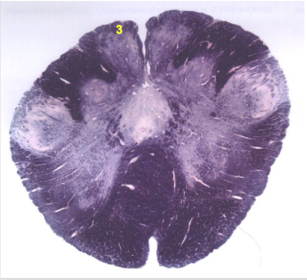

| Nucleus gracilis | |

| Nucleus cuneatus | |

| Fasciculus gracilis | |

| Fasciculus cuneatus | |

| Internal acruate fibers | |

| Lateral (external/accessory) cuneate nucleus | |

| Medullary pyramids | |

| Hypoglossal nucleus | |

| Hypoglossal nerve | |

| Dorsal motor nucleus of X | |

| Nucleus ambiguus | |

| Solitary tract | |

| Solitary nucleus | |

| ALS | |

| Medial lemniscus | |

| Medial longitudinal fasciculus | |

| Spinal tract of V | |

| Spinal nucleus of V | |

| Lateral (external, accessory) cuneate nucleus | |